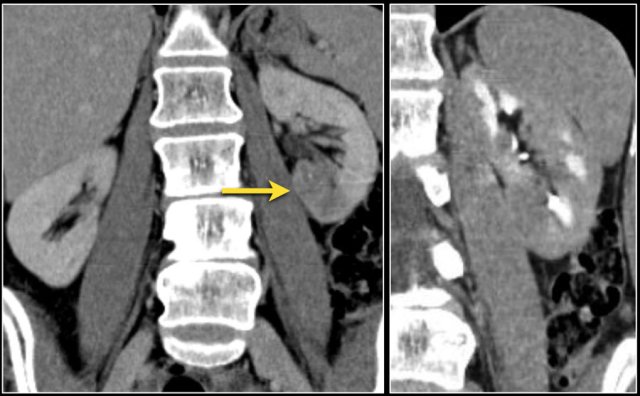

The corticomedullary phase 25-40 sec post injection is strongly recommended. It helps to differentiate tumor from pseudotumor and to assess enhancement of a lesion.

In this phase however a tumor located in the renal medulla can have the same attenuation as the surrounding parenchyma (figure).

Therefore the nephrogenic phase (±100 sec post injection) is the most important phase for the detection of a tumor.